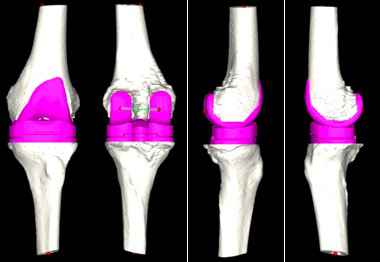

对此,张弛团队在与患者及家属充分沟通后,决定使用人工智能系统辅助置换全膝关节。专家在系统中上传患者的CT资料,人工智能便快速完成了术前规划,其模拟的假体型号及角度、位置十分精准。

人工智能术前规划模拟出精准的假体大小和位置。

术中运用后交叉韧带保留型的假体进行膝关节表面置换,术后复查照片精准复制了人工智能测量的结果。